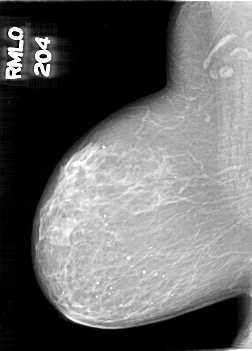

D_4098_1.RIGHT_MLO

RIGHT_MLO LINES 6661 PIXELS_PER_LINE 4771 BITS_PER_PIXEL 12 RESOLUTION 43.5 NON_OVERLAY